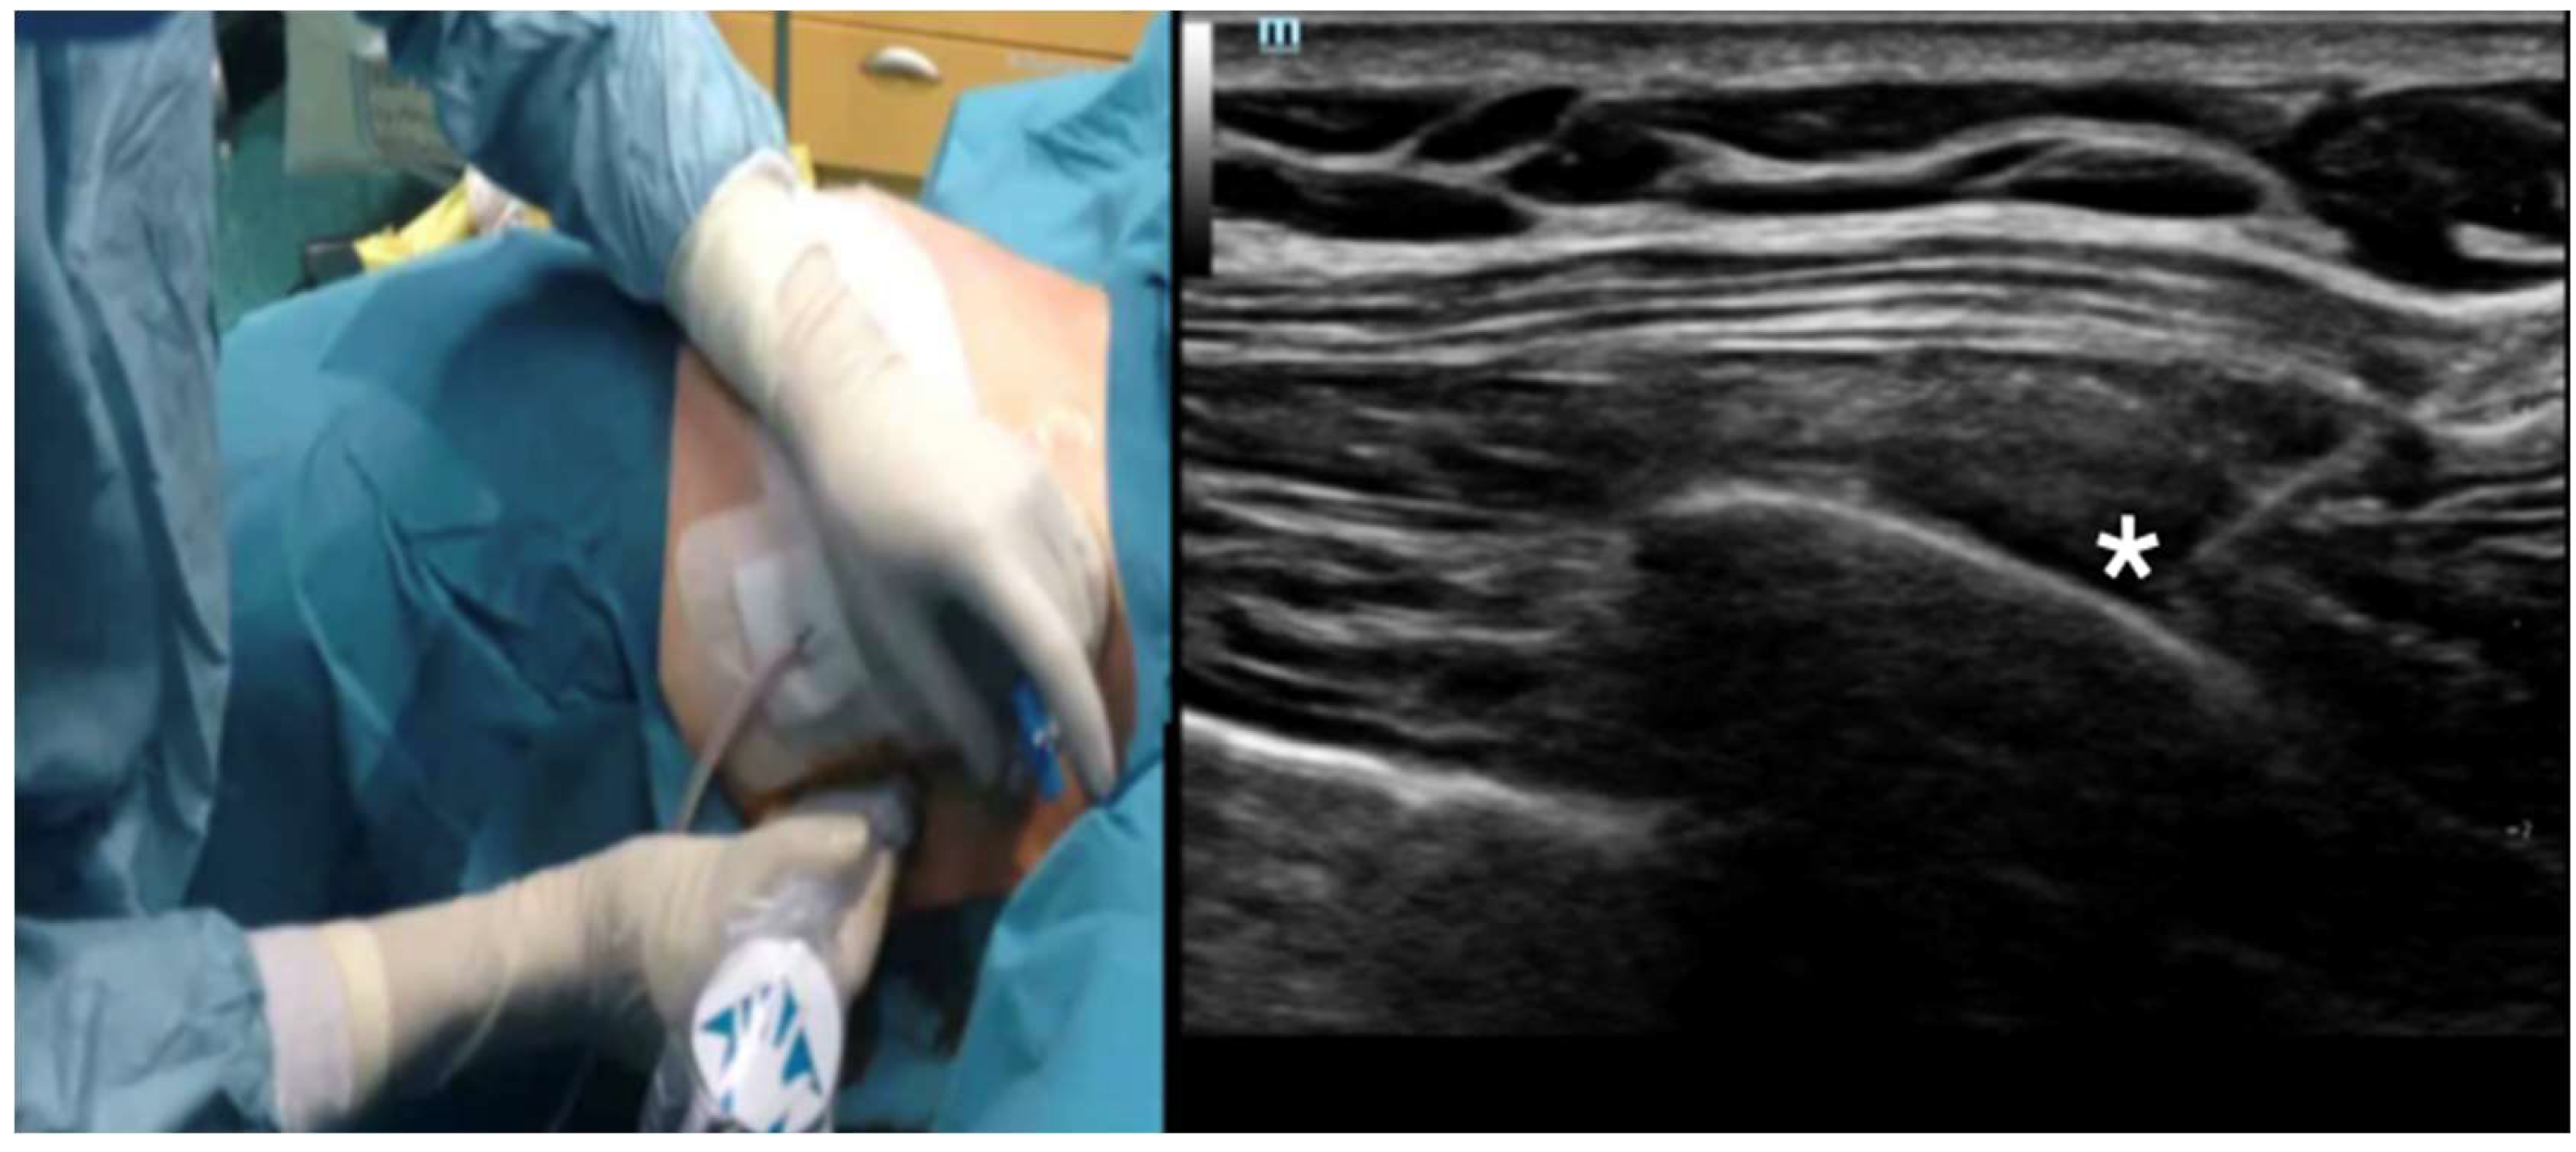

Bilateral Serratus Plane Block in a Critically Ill, Mechanically Ventilated Patient with Multiple Rib Fractures Due to Severe Thoracic Trauma: Case Report and Literature Review

3.1. Case Presentation